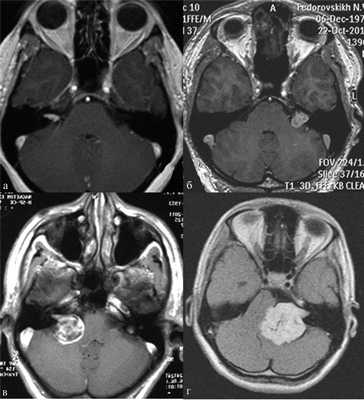

В практической деятельности наиболее универсальными являются классификации, предложенные Koos [11] и Samii [12]. Они основаны на оценке размеров невриномы и ее отношении к окружающим мозговым и костным структурам (рис. 1, 2).

Рис. 1.Иллюстрация классификации неврином слухового нерва по Koos. а — I стадия — опухоль находится в пределах внутреннего слухового прохода, диаметр экстраканальной части составляет 1—10 мм; б — II стадия — опухоль вызывает расширение канала внутреннего слухового прохода и выходит в мостомозжечковый угол, ее диаметр составляет, 11—20 мм; в — III стадия — опухоль распространяется до ствола головного мозга без его компрессии, диаметр составляет 21—30 мм; г — IV стадия — опухоль вызывает компрессию ствола головного мозга, ее диаметр более 30 мм.

Рис. 2.Классификация неврином слухового нерва по M. Samii. а — Т1 — интрамеатальная опухоль (рис. 2, a); б —Т2 — интра-экстрамеатальная опухоль; в — Т3а — опухоль заполняет мостомозжечковую цистерну; г —Т3b — опухоль распространяется до ствола головного мозга; д —Т4а — опухоль вызывает компрессию ствола; е —Т4b — опухоль грубо деформирует ствол мозга и IV желудочек.